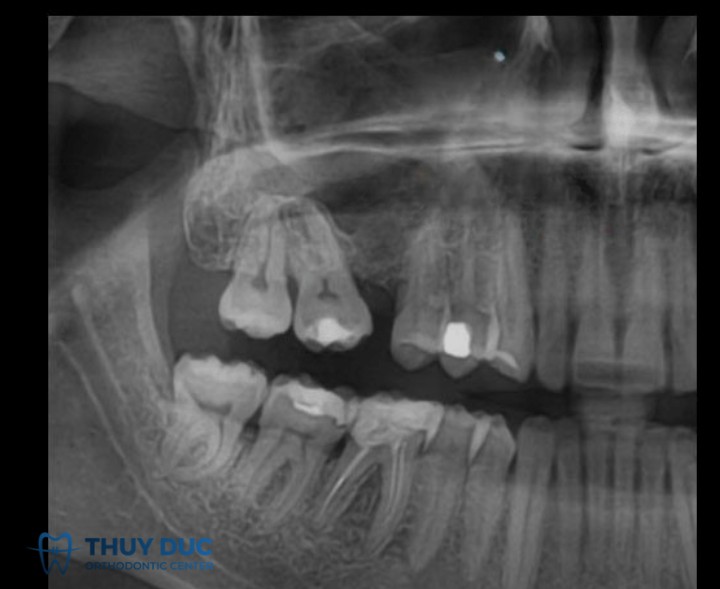

Khi một hoặc nhiều răng bị mất (do nhổ, chấn thương hoặc bệnh lý) mà không được phục hình kịp thời, các răng kế cận hai bên khoảng trống thường có xu hướng nghiêng hoặc đổ vào khoảng mất răng. Răng đối diện cũng có thể trồi xuống làm mất tương quan khớp cắn.

Một bệnh nhân mất răng hàm dưới số 6 trong thời gian dài. Răng số 5 và số 7 bị nghiêng vào khoảng trống, đồng thời răng số 6 hàm trên trồi xuống. Cần chỉnh nha để dựng trục răng 5 và 7, điều chỉnh lại răng trồi, sau đó mới phục hình bằng implant hoặc cầu răng.